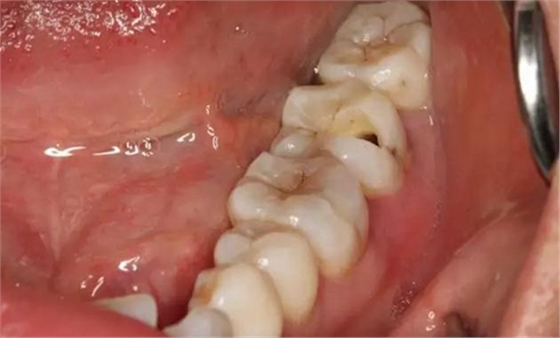

圖2. 37牙冠基本完好,松動Ⅰ度。合面有一開髓孔被棉球覆蓋,頰側(cè)牙齦輕度紅腫。